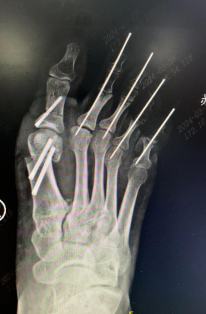

经过检查,小李的右脚除了爪形趾导致的走路疼痛外,还因为有拇外翻导致了穿鞋困难,为了帮助他回归正常的生活,手术团队准备为他进行拇外翻+爪形趾畸形矫正的手术。

术前 术后即刻

术后,复查DR片显示,小李的脚步畸形已得到矫正,经过一段时间恢复,行走步态已经和常人无异。看到脚趾终于恢复正常,再也不用忍受脚趾畸形的折磨。